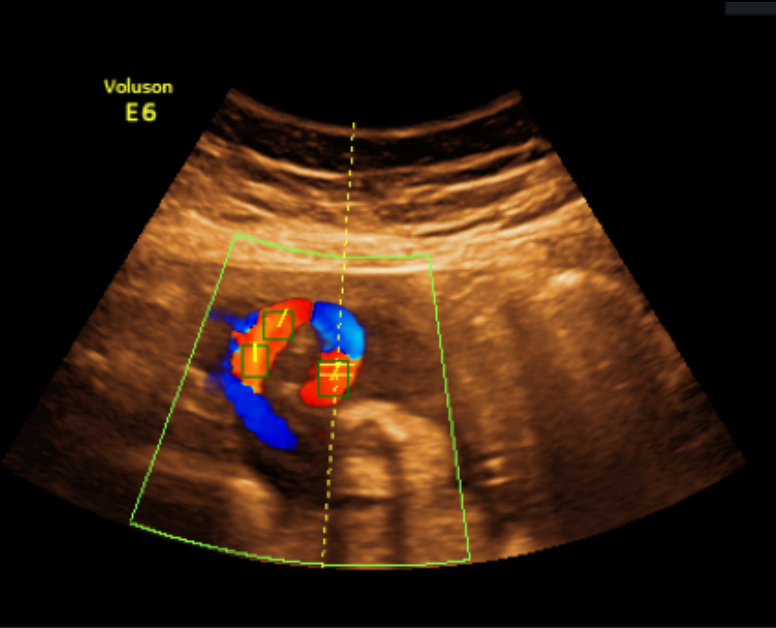

(a) Expert annotated boxes and tangential lines

Refer to caption

(b) Model predicted boxes and tangential lines

(c) Vectors pointing in direction of ultrasound source

Figure 4: Different stages in processing Color Doppler image.

Subsequently, the color Doppler images were annotated by a clinician using the open-source tool LabelMe [13]. On each image, regions corresponding to the correct anatomical site (i.e. the UA) were annotated with bounding box, which was done sparsely due to the inherent difficulty in annotating all correct anatomical sites with just bounding boxes. Finally, a tangential line going in the direction of the blood vessel were added on top of each annotated bounding box to indicate the vessel’s angle (see Fig. 4(a)).